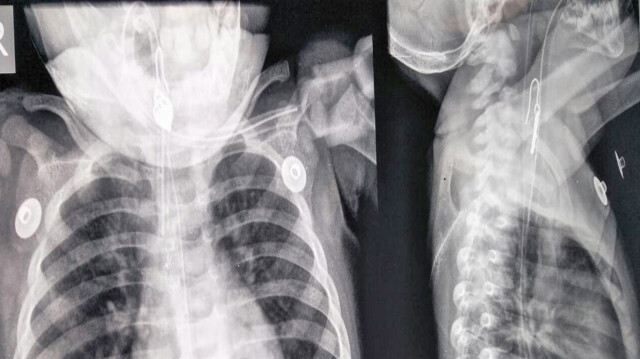

लोगों की सलाह पर ख़ुशी के परिवार वालों ने ख़ुशी को बाई जेरबाई वाडिया अस्पताल में दाखिल कराया। वाडिया के ईएनटी विभाग के प्रमुख डॉ. दिव्य प्रभात ने बताया कि जब खुशी को यहां लाया तो समझ में नहीं आ रहा था। उन्होंने आगे कहा कि डॉक्टरों की एक टीम ने खुशी की बारीकी से जांच के बाद उसका एक्सरे निकाला तो गले में अटकी हुई वस्तू नजर आई। इसके बाद खुशी को ऑपरेशन थियटर में ले जाया गया, जहां 'ब्रॉन्कोस्कोपी' की मदद से गले से इयररिंग निकाली गयी। डॉ. प्रभात के मुताबिक ख़ुशी के ऑपरेशन की भी जरुरत नहीं पड़ी, उसका एक्स्ट्युबेट किया गया और अब वह नॉर्मल है और सामान्य बच्चों की तरह खा पी रही है। यह सब हुआ मात्र आधे घंटे के अंदर।